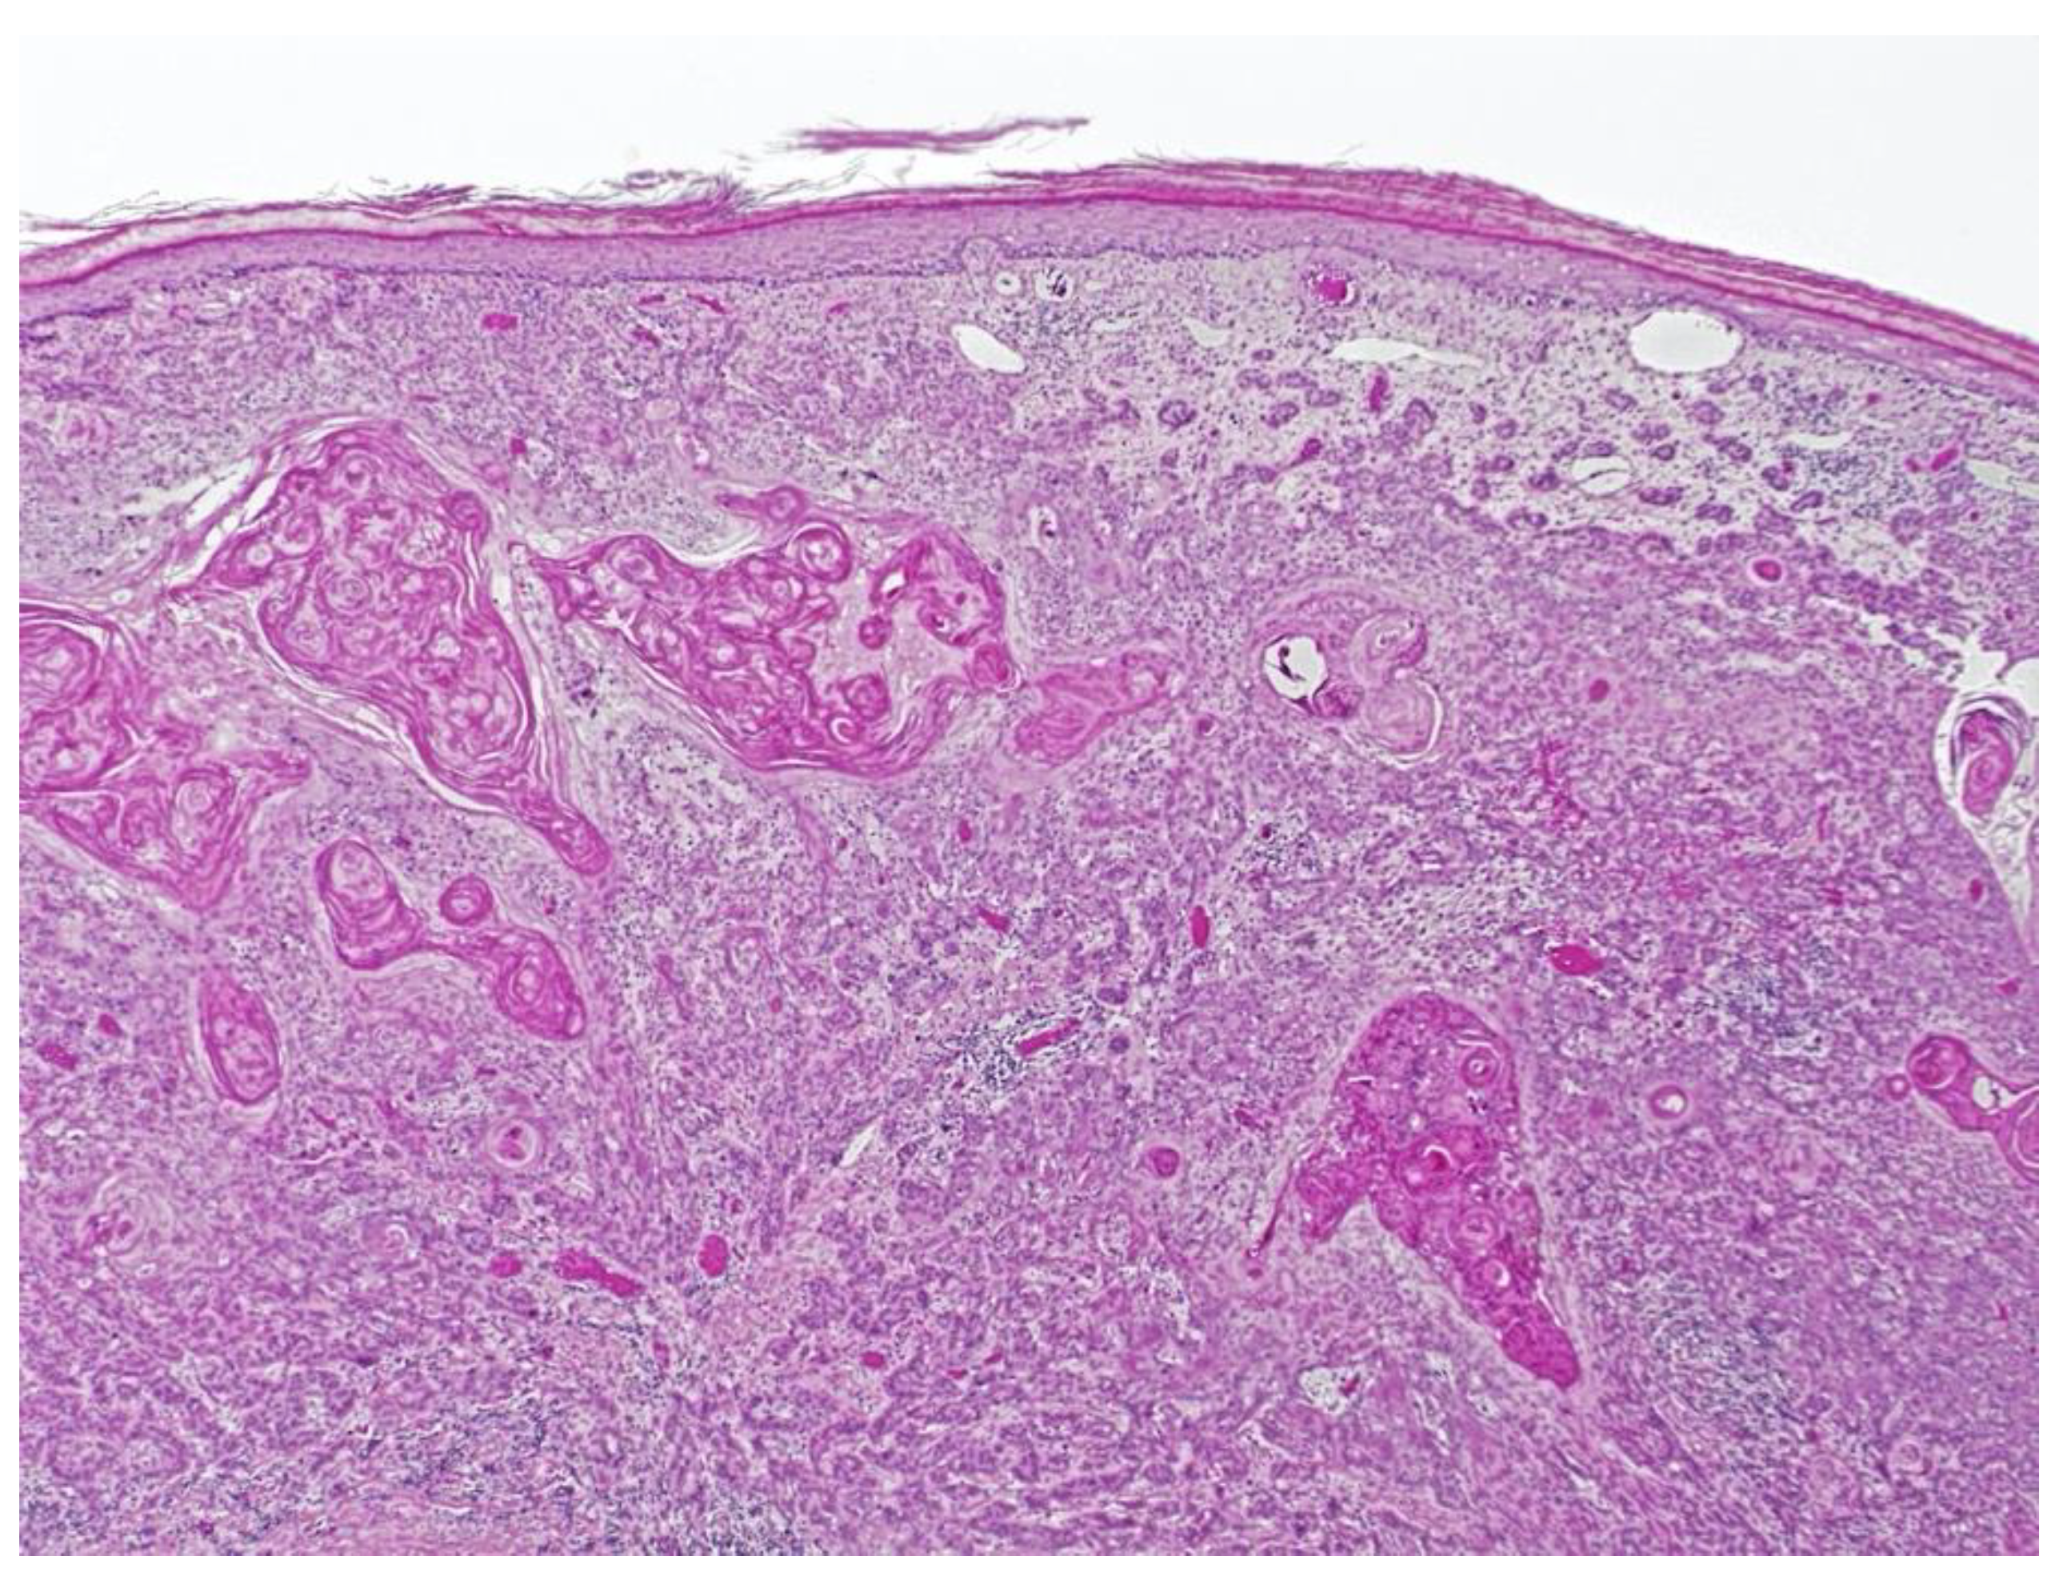

Figure 5.

Squamous cell carcinoma with perineural invasion of greater than 0.1 mm.

Ten months after Mohs surgery, the patient presented with a 2.4 cm fissured, indurated, erythematous, ulcerated plaque on the right ventral ulnar palm. (Figure 4) This was separated by 2.6 cm of normal skin from the scar from the prior C-SCC on the right hand. Punch biopsy revealed squamous cell carcinoma with perineural invasion involving a 0.1 mm cutaneous nerve. (Figure 5) With her scar contracture and functional impairment in that hand, she was referred to orthopedic oncology. After discussion of risks and benefits for excision with secondary intent healing versus a ray resection, the latter was agreed upon.